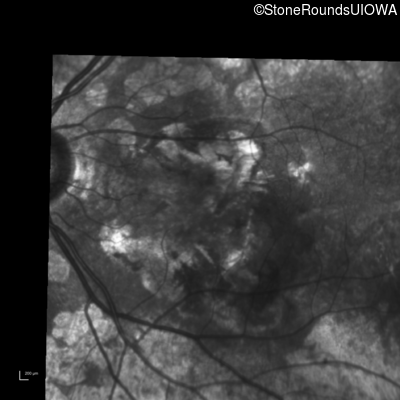

Fluorescein Angiography - Right - 20/125

Exemplar